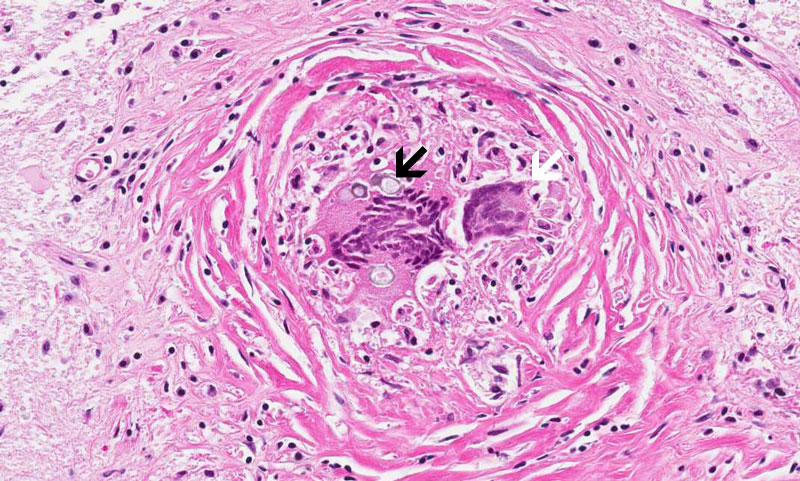

Hematoxylin & eosin

Area 2: The granulomas are composed of histiocytes in concentric arrangements forming nodules. At the center of the granulomas are mulitnucleated ginat cells containing the fungus.

• In Slide #1, the salient pathologic change here is a necrotizing granulomatous inflammation of the leptomeninges associated with foreign body type giant cells and round inclusions that are morphologically consistent with Coccidiodes species. These organisms can be well demonstrated by PAS stain (see below). Note that there is fibrotic thickening of the leptomeninges (outlined by the arrows). The granulomas are only accompanied by a small amount of lymphocyrtes. Note that the granulomas are limited to the meninges.

• The spheres of Coccidioides are among the largest that are seen in histologic sections and range from 30 to 60 μm. Most of the fungal organisms are likely to be non-viable in this case because of aggressive fungal therapy. The impressive foreign body type giant cell reaction is likely a reaction to the non-viable spores.